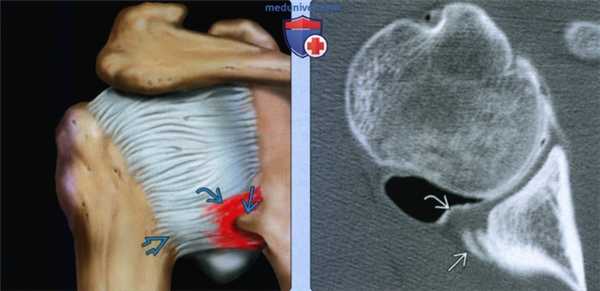

(Слева) На рисунке показано повреждение Беннетта с окружающим отеком капсулы. Пред полагается, что это повреждение сопровождается гетеротопной оссификацией или тракционным энтезофитом в месте прикрепления заднего пучка нижней суставно-плечевой связки. Это повреждение наблюдается, в основном, у питчеров в бейсболе.

(Справа) На осевой КТ-артрограмме у бейсбольного питчера определяется повреждение Беннетта по задненижнему краю суставной впадины. Спортсмена беспокоила боль при внутреннем импиджменте. Задняя губа интактная.